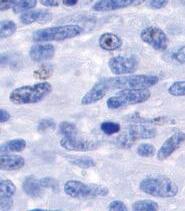

Questo vale anche per le cellule leucemiche. Una caratteristica di questa forma di tumore del sangue è l’eccesso di produzione di globuli bianchi, i pazienti affetti da leucemia muoiono principalmente, perché queste cellule bloccano la circolazione del sangue. In molti casi i leucemici muoiono per il cedimento di vari organi, in particolare ‘gli organi filtro’: il fegato e la milza. Milioni di globuli bianchi invadono questi organi attraverso il flusso sanguigno. Queste cellule cancerose producono immense quantità di enzimi che digeriscono il collagene, digerendo letteralmente questi organi dall'interno.

La foto nella pagina a fianco mostra una sezione trasversale al microscopio del fegato di un paziente con ‘leucemia linfatica’. Ciascuno dei piccoli puntini viola nella foto è un globulo bianco (in questo caso linfocita) che ha invaso il tessuto del fegato (aree rosa).

Considerando l’enorme quantità di questi puntini viola e il numero di enzimi che assimilano il collagene che ciascuno produce, è facile prevedere l’ingente distruzione del tessuto connettivo e il danno apportato all’organo da questo tipo di cancro.

La leucemia è un buon esempio di come la comprensione dei meccanismi delle cellule tumorali, la produzione di enzimi che digeriscono il collagene da parte dei globuli bianchi, per poter studiare terapie efficaci.

Immagine al microscopio della leucemia linfatica

Globuli bianchi affetti di cancro (linfociti) invadono il fegato L’enorme quantità di collagenasi prodotte da queste cellule distruggono l’organo e causano insufficienza epatica.